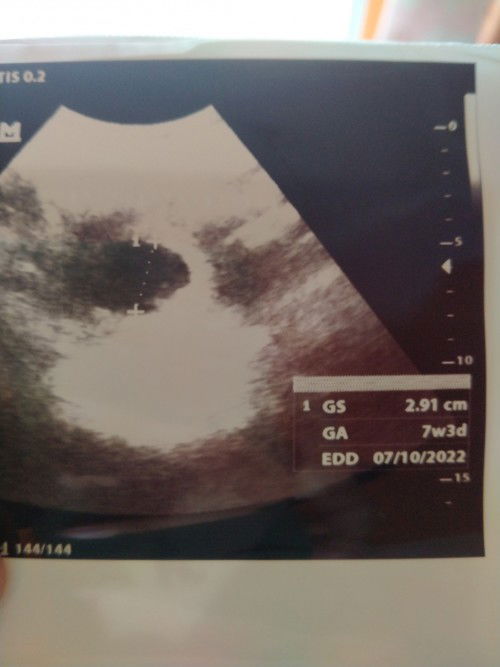

Mau nanya bun , sy hamil 25 minggu anak ke-2 kalo di usg jk nya perempuan yg anak pertama laki2., sampai skrg sy blm ngerasain gerakan janin bun hanya kedut2an aja. Kadang malah ga mgerasa apa2. Tp di usg selalu normal , wktu kk nya aktif bgt bun diperut , sy selalu worry bun. Apakah ada yg sama kaya sy bun kehamilan anak ke 2 malah janin nya pasif bgt ? #bantusharing